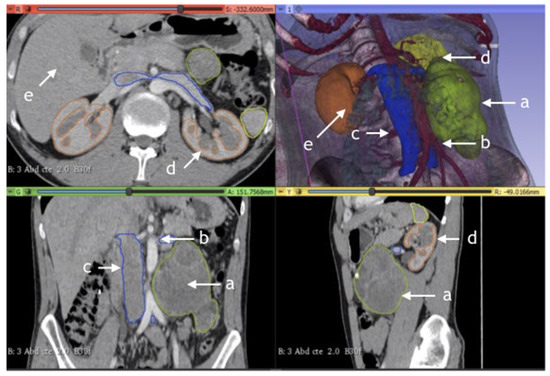

Table 1 summarizes the clinical information of the patients included in this study (n = 60). The median age of all patients was 25.50 (IQR = 17–56). The median size of the residual tumor was 89 cm3. There were no significant differences between the two subgroups. Figure 1, Figure 2, Figure 3 and Figure 4 are examples of prospective cases in which the tumor analyzed pre-operatively with 3D images is totally resected by a young surgeon. No death occurred during the intraoperative and perioperative period in this study.

Figure 4. Para-aortic residual mass, post-chemotherapy germ cell tumor. Example of CT-rendered 3D reconstruction: (a) tumor; (b) aorta; (c) v. cava; (d) kidney; and (e) spleen.